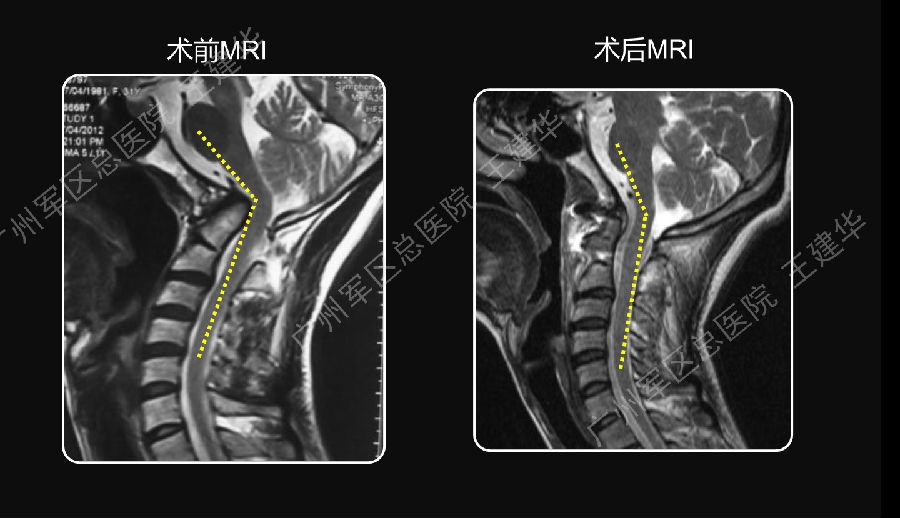

术前术后对比

手术前后对比

手术后CT显示,陷入枕骨大孔的齿突获得下拉复位

术后MRI发现,患者的颅底凹陷,脊髓空洞和Chiari畸形均获改善